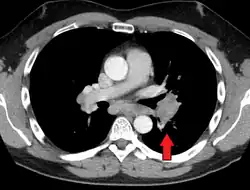

Hilar adenopathy especially on the person's left (AP CXR)

Hilar adenopathy especially on the person's left (coronal CT)

Hilar adenopathy especially on the person's left (transverse CT)